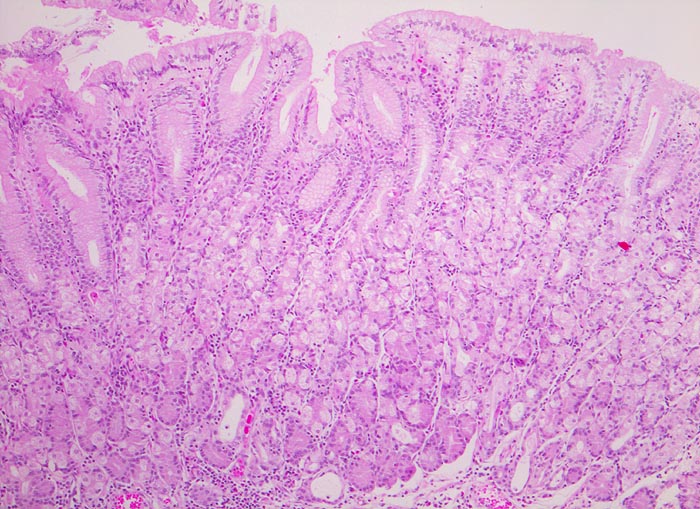

PathoPic – image database / PathoPic ID 4336 - normale Magenkorpusmukosa

normale Magenkorpusmukosa

Magenkorpus

Magenkorpusmukosa mit relativ kurzen Foveolae. Wegen der fehlenden Entzündung ist das Stroma (=Lamina propria) zwischen den magenspezifischen Drüsen und den Foveolae kaum erkennbar. Die Belegzellen sind an ihrem hellen Zytoplasma und ihrer kugeligen Form erkennbar, die Hauptzellen an ihrem eosinophilen Zytoplasma und die Nebenzellen an den basalständigen Kernen.

Histologie

50